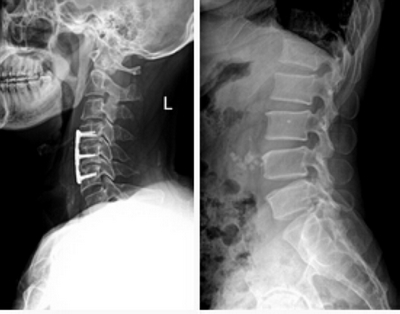

★適用于全身各部位攝影,包括常規攝影(立位攝影、臥位攝影等,如胸片、頸椎、腰椎、腹部、頭顱、四肢等)和特殊攝影(傾斜攝影、角度攝影等,如瓦氏位、骶髂關節、髕骨軸位、跟骨軸位等)。

在常規拍片中,往往由于影像的重疊或體位等因素造成病灶征象漏診,而動態攝影中則更易于發現這些病灶。